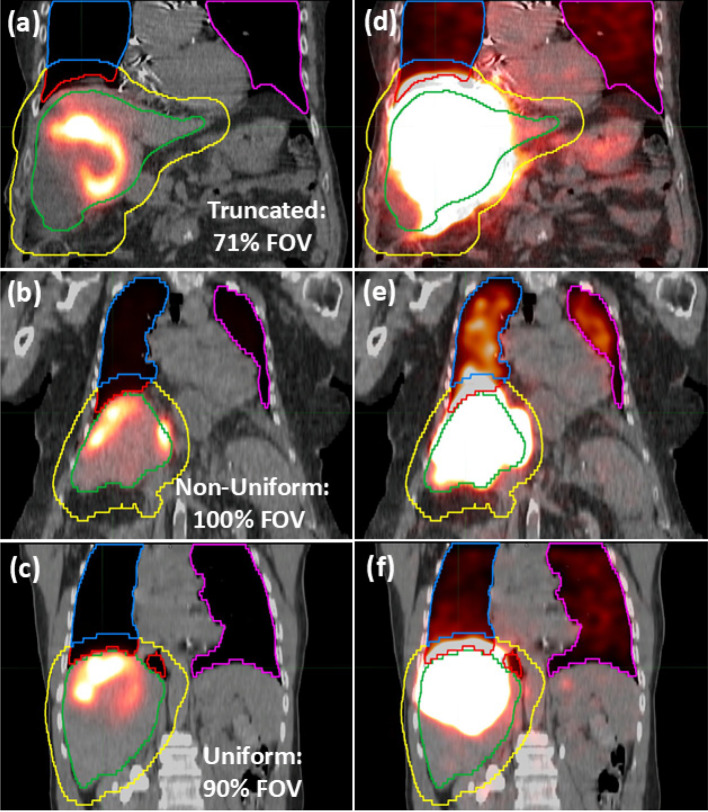

Methods: Lung truncation was simulated in 56 cases with adequate (> 90%, mean: 98%) lung coverage in MAA-SPECT/CT by removing slices in ~ 5 mm increments from the lung apices to the diaphragm. A wide range of lung coverages from 100% to < 1% in ~ 2% increments were created. LSF and LMD were calculated with four methods. (1) 2D planar imaging standard (not truncated), truncated lung SPECT/CT data was: (2) used with no corrections (SPECTTrunc), (3) uniformly extrapolated to full lung coverage (SPECTUniform), (4) fit with an empirical model to predict lung counts at full lung coverage (SPECTFit). To determine counts for LSF, full lung volumes, those modified at the lung/liver boundary (Lungs 2-cm), and those isolated to the left lung (Left Lung) were used. The correction methods were then applied to 31 independent cases without full lung coverage (< 90%, mean: 74%). The variations in LSF and LMD estimates from each correction method were analyzed.